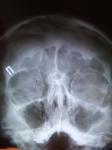

Здравствуйте. Меня беспокоит чувство давления в гайморовой пазухе слева, ближе к носу (на протяжении уже долгого времени периодически появляется на 2-3 дня и исчезает). Выделений никаких нет, температуры нет, немного увеличен лимфоузел с этой стороны. На данный момент есть защемление плече-лопаточного нерва (лечу). С чем это может быть связано?

Здравствуйте! Скорее всего, у вас киста левой гайморовой пазухи по крайне боковой стенке. Для уточнения диагноза следует сделать КТ придаточных пазух носа.

Если боли неврологической природы, то ванны могли оказать положительный эффект. Киста, как правило, не дает болей, а оказывает давление на стенки пазухи.